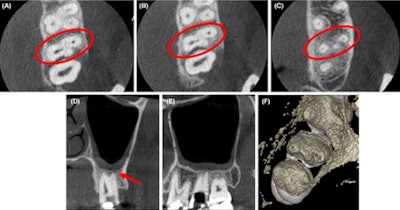

(A-C) Axial CBCT images in the cervical, middle, and apical region of the man’s molar. (D) The coronal section showed the apical split of roots and early periapical radiolucency in the palatal root (red arrow). (E) The sagittal section shows the gouging of the floor. Images courtesy of Marya et al. Licensed by CC BY 4.0.

Imaging aided in managing a man’s atypical root canal anatomy in which the distobuccal canal of his maxillary second molar was close to the palatal root canal with partially fused roots.

From the clinical and imaging findings, clinicians diagnosed the man with pulpal necrosis with symptomatic apical periodontitis and then executed appropriate endodontic treatment, the authors wrote.